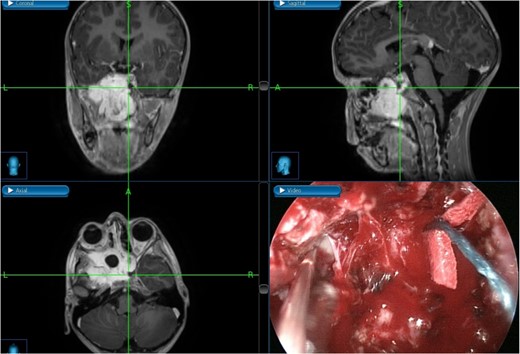

The patient underwent an endoscopic four-handed transseptal resection of the left JNA following uneventful embolization. Intraoperative endoscopic examination of the nasal cavity revealed a bluish mass in the left nasal cavity and a severe right-sided deviation of the nasal septum. A septal window was created, allowing bilateral access to the tumor. The tumor was dissected and removed, separating it from its bony attachments to the nasopharynx and clivus. Dissection extended to the bilateral sphenoid sinuses, allowing for complete tumor excision from the carotids, cavernous sinuses, infratemporal fossa, and skull base with navigation assistance (Fig. 2). The patient was asymptomatic on close follow-up until 8 months later, when he had intermittent self-limiting episodes of epistaxis without nasal obstruction. Examination revealed bilateral crustations and a small left nasal mass, with no obvious source of bleeding. Confirmation of tumor recurrence was done, and the patient underwent a successful second procedure for tumor resection.

Tumor dissection from the right ICA using intraoperative navigation assistance,with real-time display of instrument location in axial, coronal, and sagittal views.